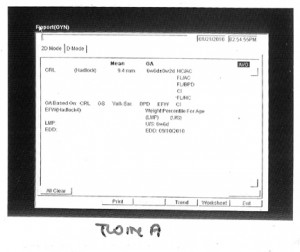

Before I go to sleep, I’ll post the first images and stats of our twins below – twin A (lower in the uterus) and twin B. Love you all!